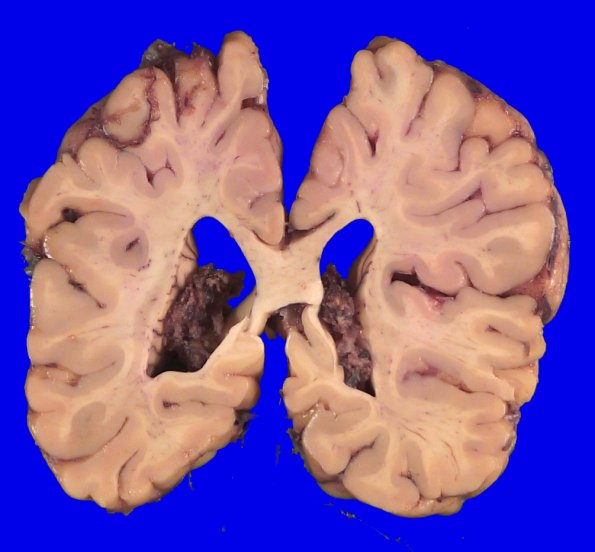

11B3-5 The cerebral cortex continues to show greater loss in the depths of sulci, particularly in the superior/middle frontal gyri. The lateral ventricles show global ventriculomegaly.